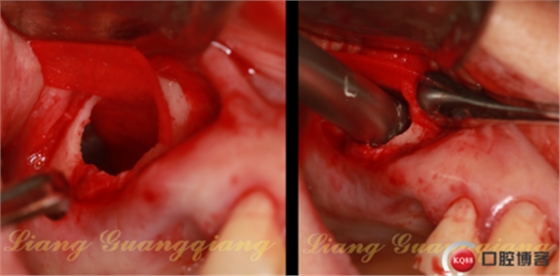

開孔鉆配合停止環(huán),停止環(huán)從1mm逐漸增加,直到有落空感為止。連接水壓系統(tǒng),連接一次性注射器,1mm生理鹽水,橡皮堵緊緊堵住孔,輕壓將生理鹽水推入,在沒有開窗之前已經(jīng)將頰側(cè)上頜竇膜剝離

第三代產(chǎn)品中的開窗鉆中間增加了柱形定位柱,比周邊的齒狀邊緣長出1mm,剛好可以插入開孔鉆制備的小孔,切割時不會滑動。由于頰側(cè)上頜竇膜已經(jīng)被水壓剝離,所以大膽切下去,幾秒鐘完成開窗。

一次性注射器,連接50ml注射器上的針頭,輕輕刺入囊腫外側(cè)壁,緩慢吸出里面的液體。